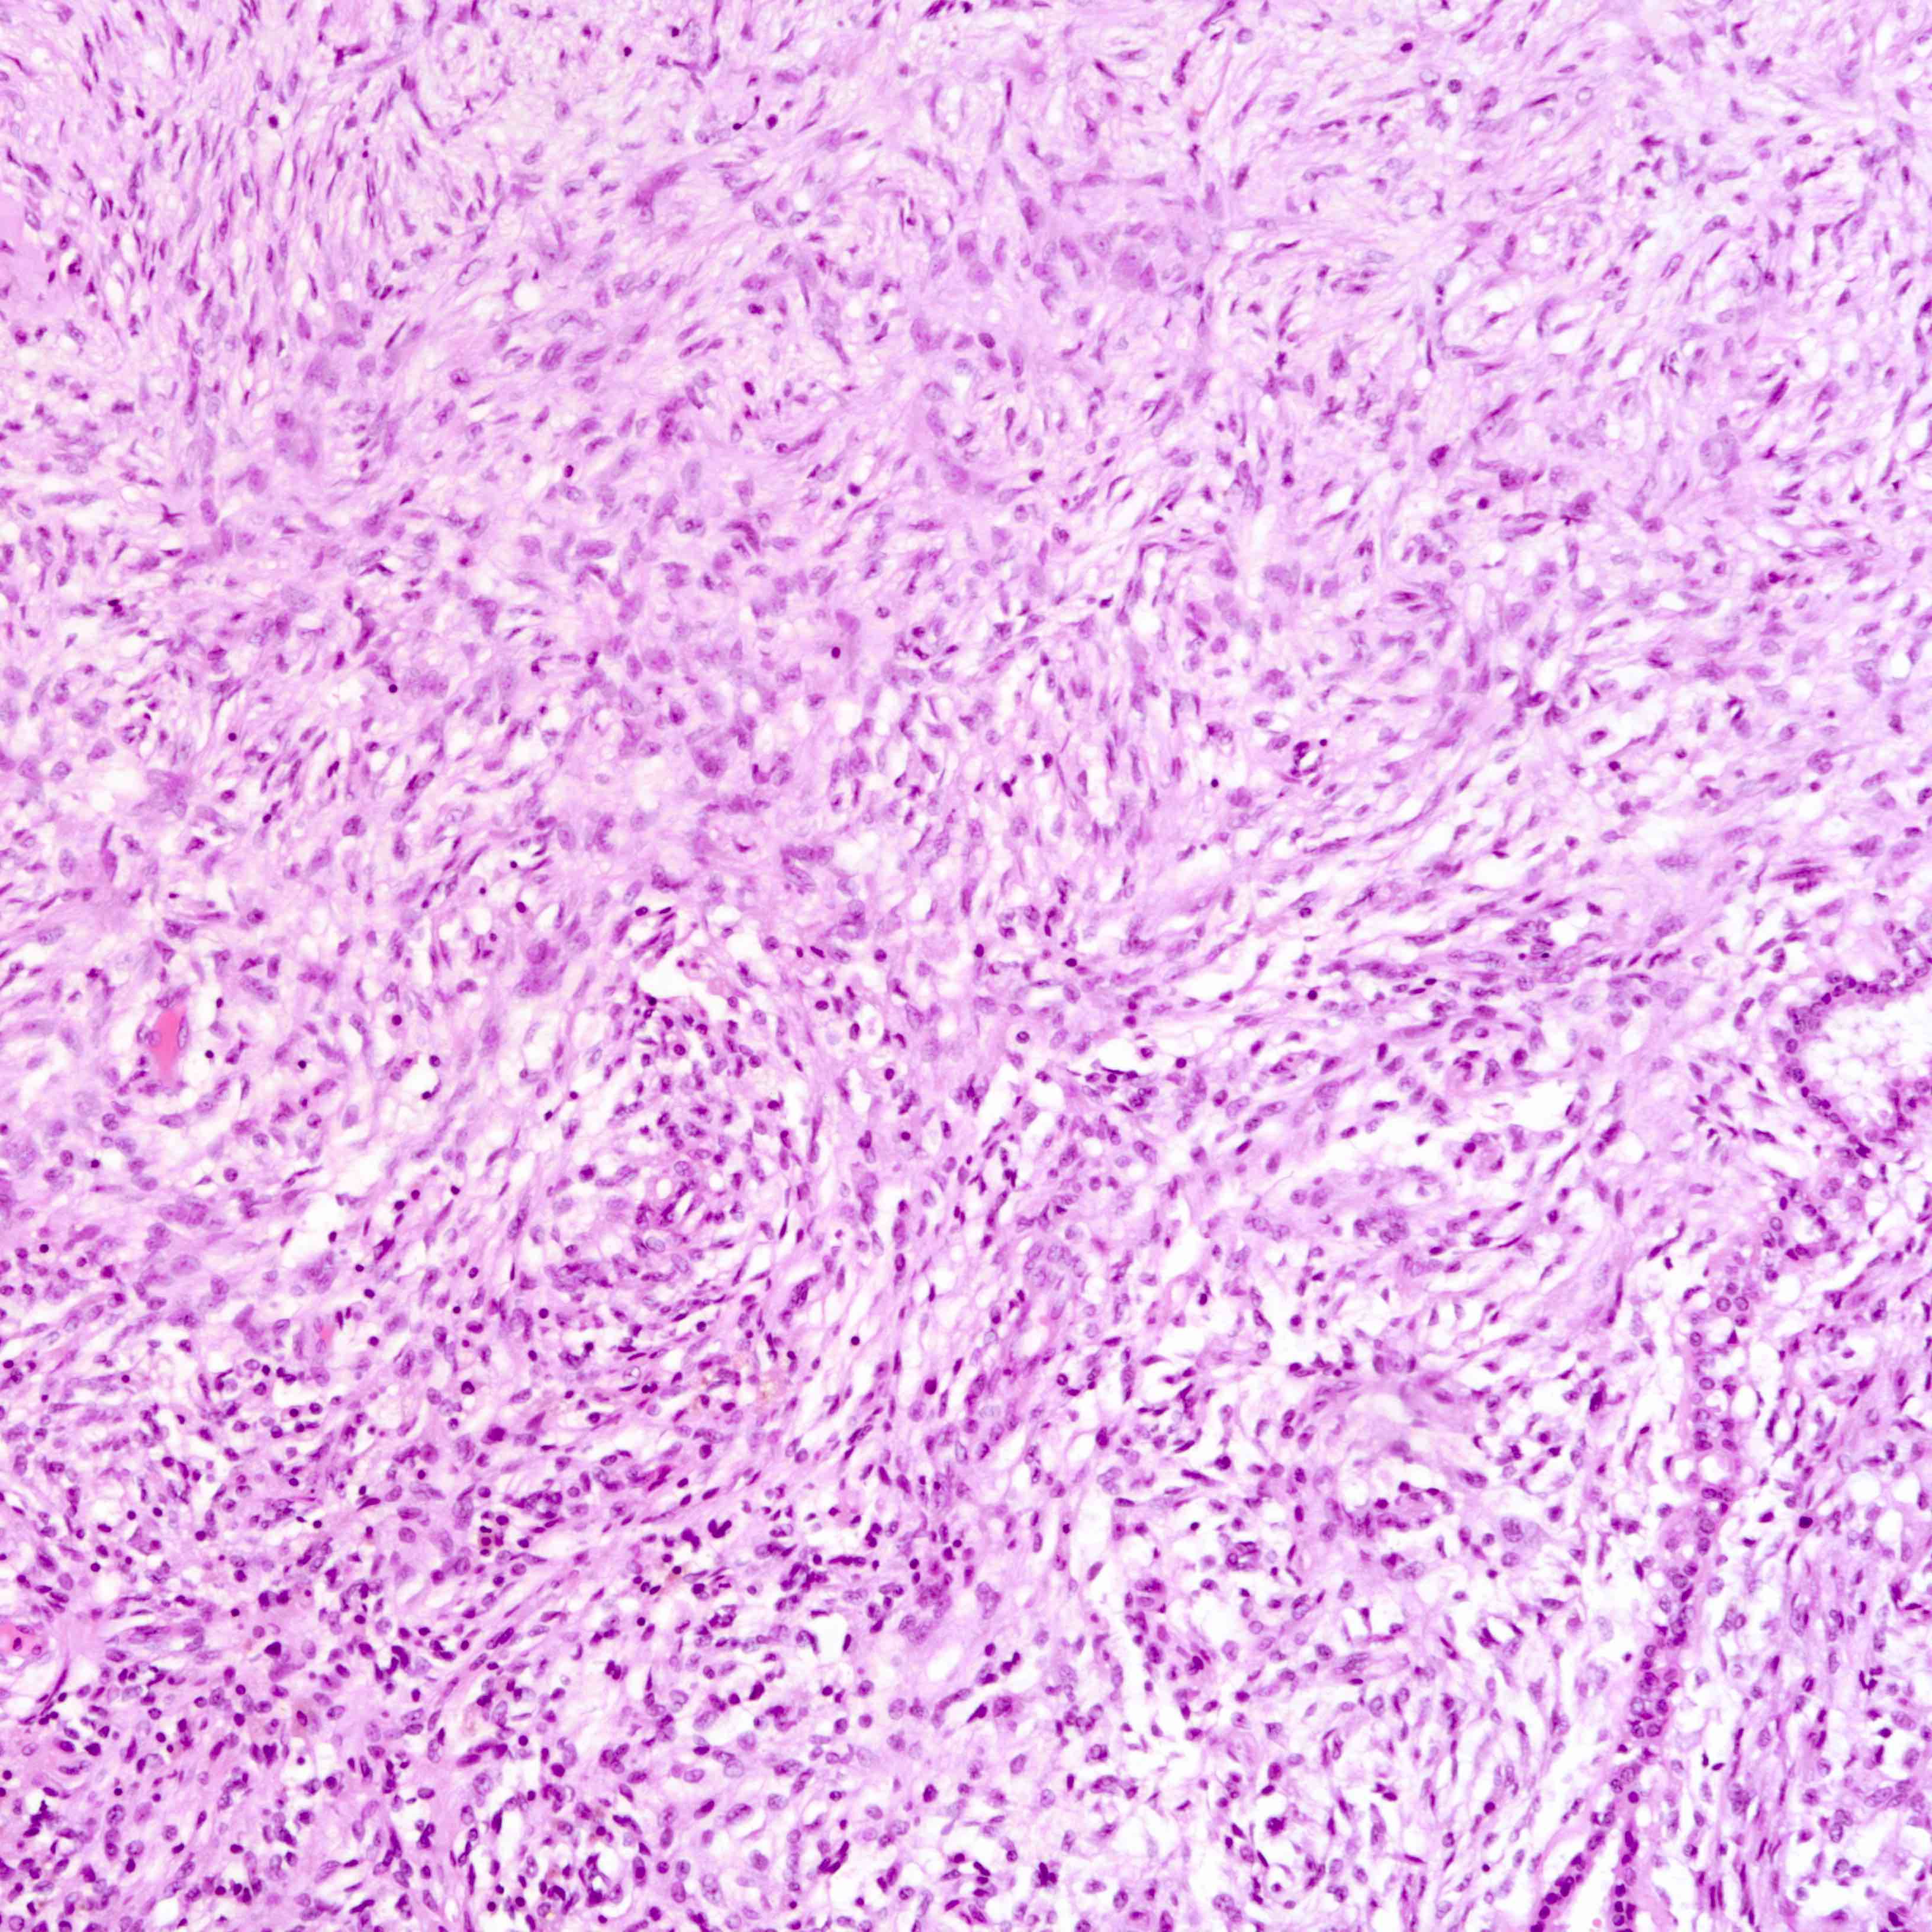

Microscopic (histologic) images

Contributed by Joshua J.X. Li, M.B.Ch.B. and Gary M. Tse, M.B.B.S.

Malignant phyllodes tumor